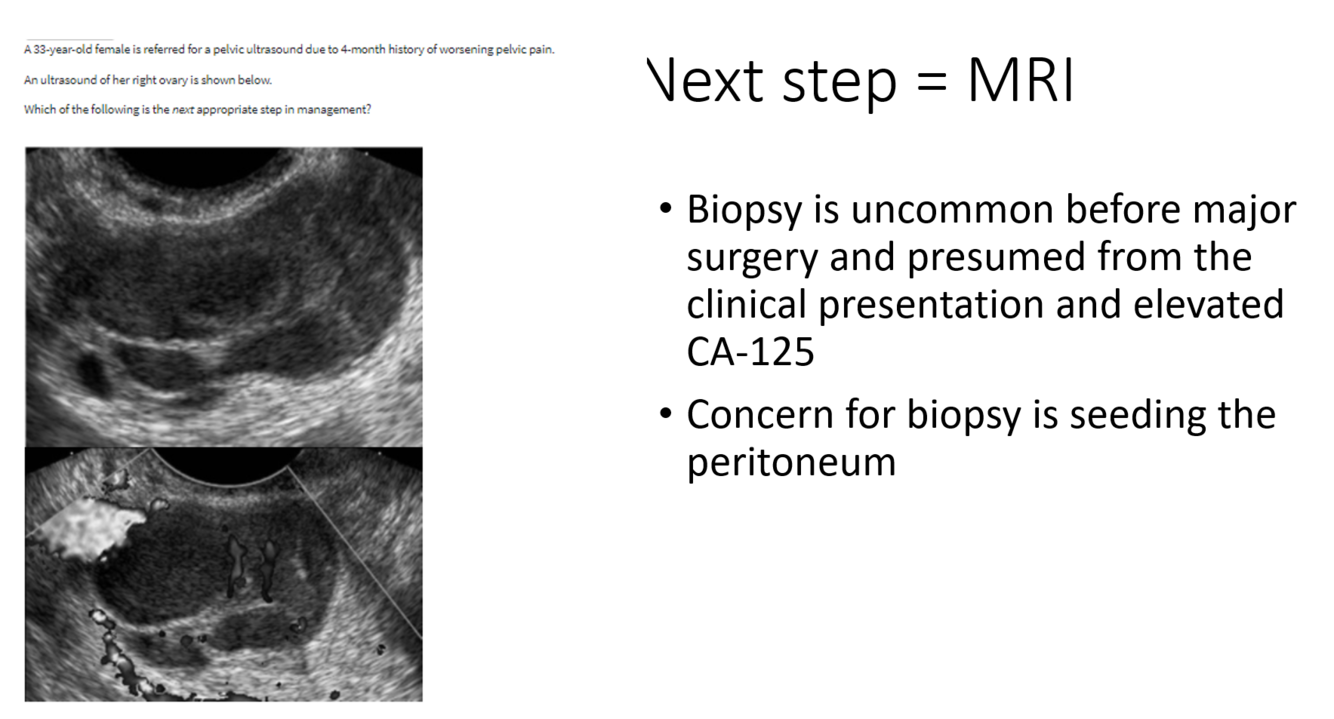

right ovarian mass shown in the image.

Next step?